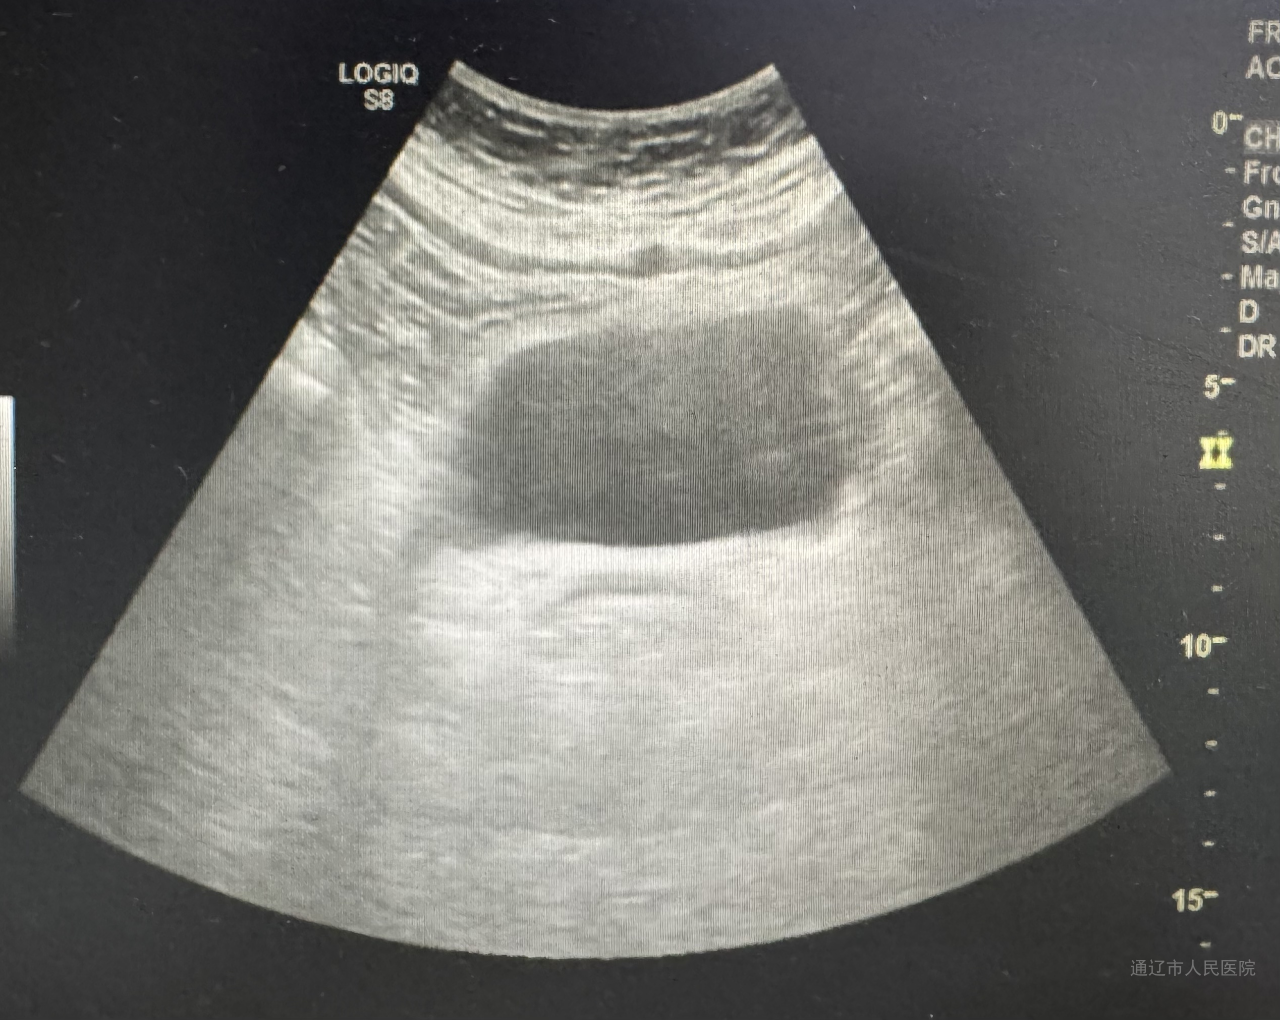

44岁患者左某某痛经10年加重,子宫增大如孕20周(18.3x12.3x17.4cm),经内分泌会诊诊断合并2型糖尿病性酮症、继发贫血及肿瘤标志物CA125>1000。经血管介入科行子宫动脉栓塞止血治疗,后经内分泌科调整血糖后再次转入我科行腹腔镜手术,此次手术依旧由白鹏来主刀,佟金荣、周所霞、程红岩协助,通过旋切器逐步缩小巨大子宫。快速病理结果显示为良性,术后第三天,患者术后第三天恢复良好。